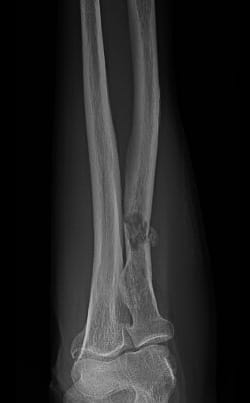

When a tumor of musculoskeletal tissue is cancerous, it is called sarcoma. It is the job of the orthopedic oncologist to diagnose these tumors and determine if they have spread.

In addition to sarcoma, orthopedic oncologist also treat lymphoma, multiple myeloma and metastatic cancers that come from other areas of the body such as the breast, lung, prostate, kidney and thyroid gland. Orthopedic oncologists are crucial contributors to the treatment plan for these patients as they can provide treatment options that have the potential to greatly improve quality of life. Orthopedic oncologists also treat non-cancerous tumors of the musculoskeletal system such as lipomas, neurovascular tumors, bone cysts, fibrous tumors and many others.

In patients with musculoskeletal tumors, surgical removal of the tumor will often be the first recommendation, followed by surgical reconstruction of the affected area to restore function. Additional treatments may include: